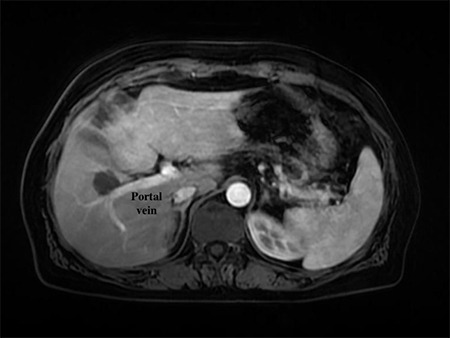

Methods: Between January 2019 and January 2022, percutaneous MWA procedures were performed for 50 liver tumors. These lesions were situated in close proximity to anatomically essential structures, with a maximum distance to surrounding structures being 10 mm. Because of comorbid lung diseases, patients could not undergo deep anesthesia. Regular follow-ups were performed using blood tests and dynamic contrast-enhanced computed tomography or magnetic resonance imaging.

Results: The patient cohort consisted of 30 (68%) men and 14 (32%) women, with a mean age of 64.36±11.65 years (range: 40-80 years). The lesions were challenging to access and were located in proximity to critical structures such as the diaphragm (32, 64%), gallbladder (8, 16%), major vessels (5, 10%), and heart (5, 10%). During the follow-up period, 10 patients (23%) had local tumor recurrence and 14 (32%) had new primary foci in a different location and metastasis [liver (10) and non-liver organs (4)]. No major complications developed, and 21 of 44 patients experienced minor complications, which were treated with local medications during follow-up.